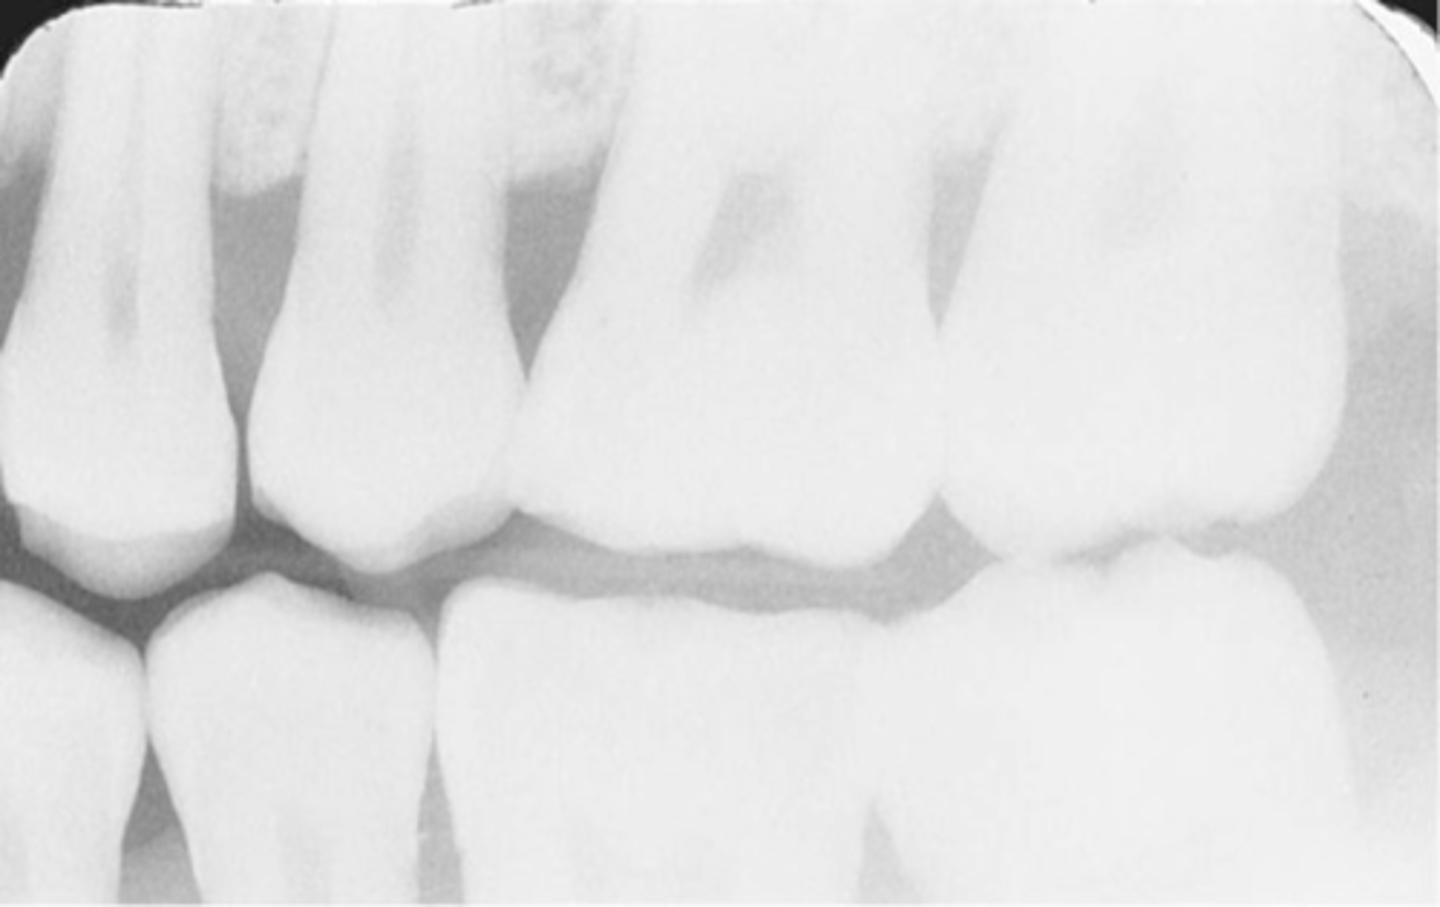

Incorrect Vertical Angulation-->Elongated Images

-Teeth appear long and distorted

-Vertical angulation was insufficient or too flat, resulting in images that are longer then the actual teeth.

-Occurs more often with the bisecting technique

-To prevent use adequate vertical angulation

Tube Head & PID-->Elongation of the Image

-Bisecting technique error

-Insufficient Angulation (not steep enough), causing elongation or increased anatomy of the teeth and cutting off apex.

3. Elongation of the image: Insufficient vertical angulation